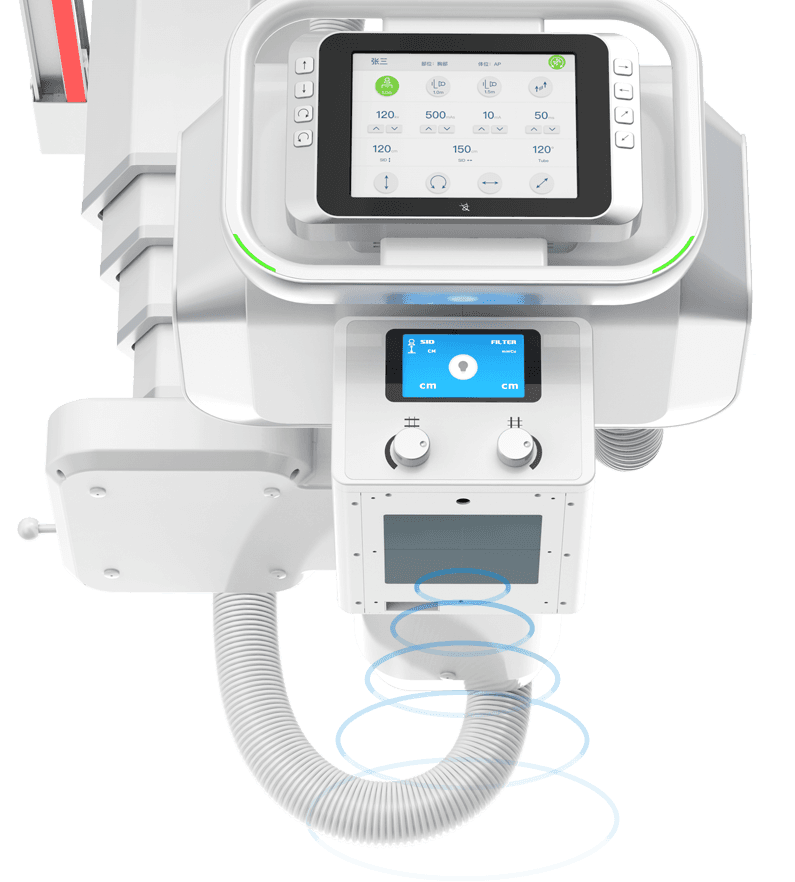

无线遥控操作

配备无线遥控器,遥控灵敏,设备运动反应迅捷,

全程支持隔室遥控操作。 -

机架内置语音对讲系统

机身内置专业医用对讲系统,语音系统采用高保真音效设计,音质清晰洪亮。

操作医师可隔室进行语音指导摆位摄片,患者在机房内可清晰接受室外操作医师语音指令,提升摆位摄片检查的安全性与效率。